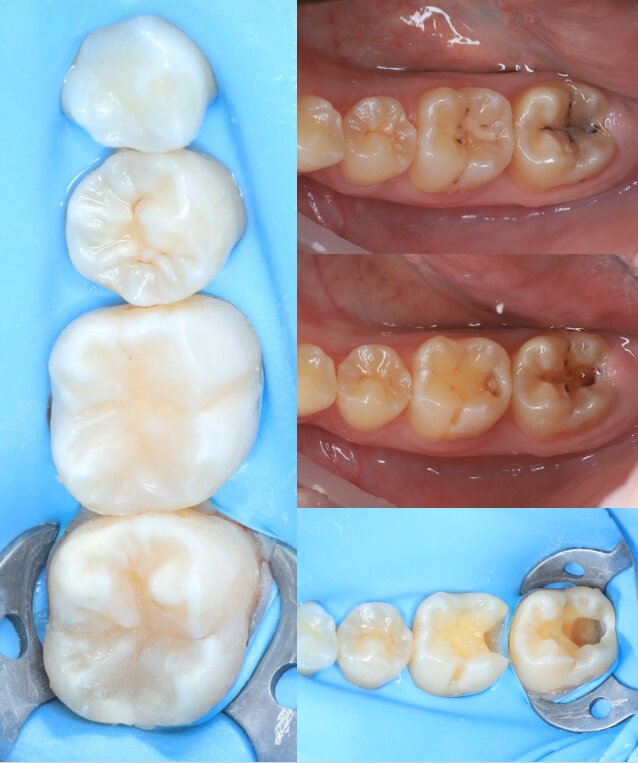

Портфоліо лікаря

У портфоліо представлені реальні клінічні випадки з практики лікаря — від первинного стану до результату лікування. Кожен кейс демонструє індивідуальний підхід, сучасні методи лікування та увагу до деталей